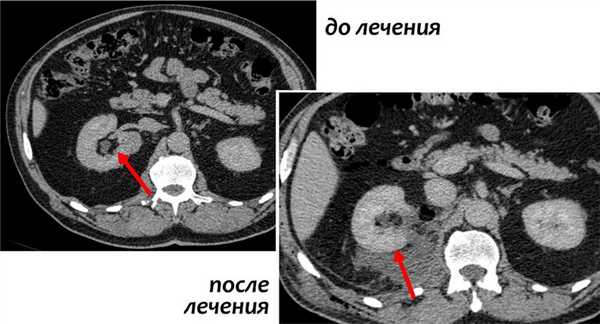

В зависимости от стадии и расположения опухоли, хирургическим методом может быть удалена только опухоль с окружающей частью почки — так называемая резекция почки, либо целая почка с опухолью — нефрэктомия. Надпочечниковая железа и жировая ткань вокруг почки также может быть удалена вместе с почкой, если возникнет необходимость.

Резекция почки

В ходе данной процедуры, хирург удаляет только ту часть почки, которая содержит опухоль, оставляя оставшуюся ткань почки неповрежденной. В настоящий момент это предпочтительный метод лечения для пациентов с ранней стадией рака почки. Часто резекции вполне достаточно для удаления одиночных небольших опухолей до 4 см в диаметре.

Также этот метод может применяться у пациентов с бОльшими образованиями, до 7 см. Специалистами НИИ онкологии им. Н.Н. Петрова успешно выполнялись вмешательства на опухолях размерами 10 и более см, однако такие операции возможны только в отдельных случаях, с учетом анатомии опухоли.

Современные исследования показали, что отдаленные результаты у пациентов, перенесших резекцию почки, почти такие же, как у пациентов, у которых почка была удалена. Однако несомненным плюсом остается сохранение большей части почечной функции.